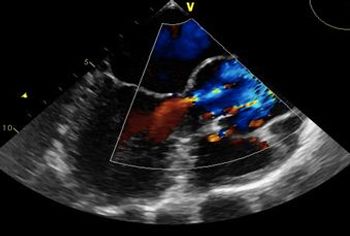

Here’s a quiz about enterovirus, PFO, diastematomyelia, the depression/asthma connection, and an HIV complication. Can you answer the 5 questions correctly?